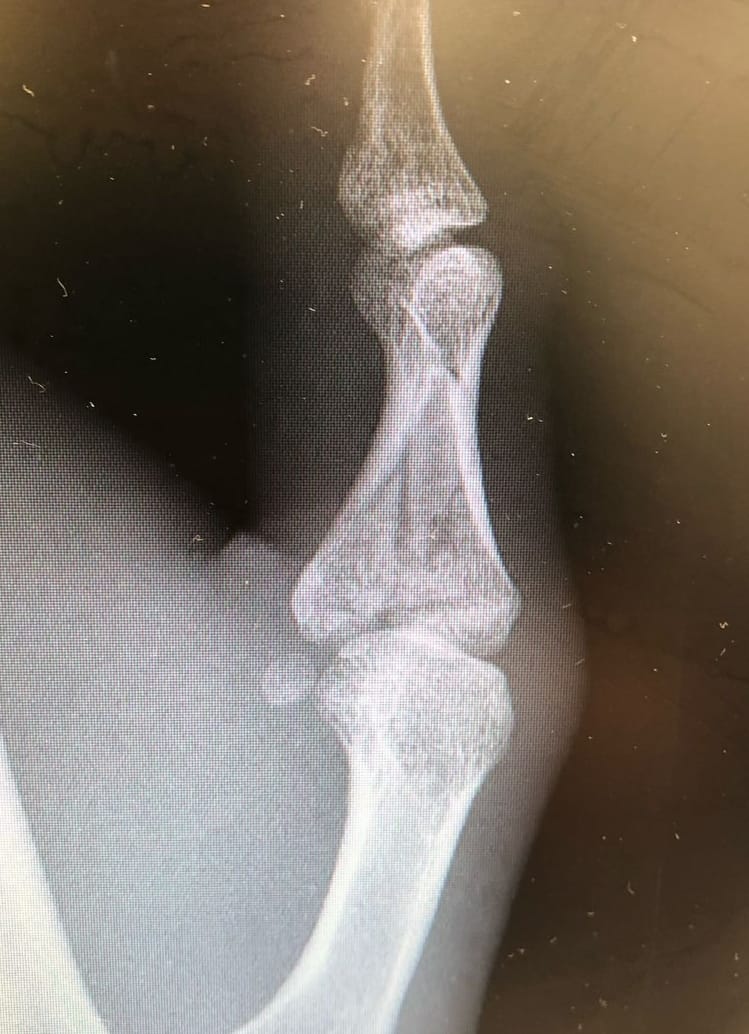

- Intra-articular fractures

- Open reduction and internal fixation